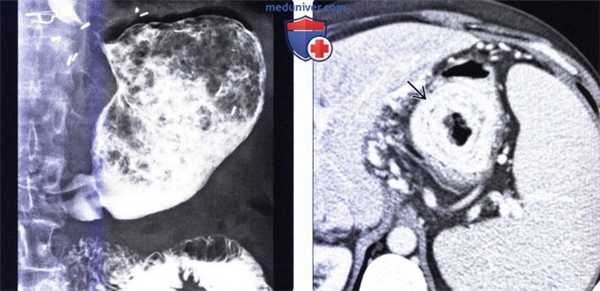

(Слева) На рентгенограмме, полученной при рентгеноскопии верхних отделов ЖКТ у мужчины 60 лете жалобами на раннее насыщение, возникшее несколько лет спустя после ваготомии и резекции желудка по Бильрот-1, определяются признаки выполненного ранее оперативного вмешательства, а также большой неоднородный «мячик» в желудке, состоящий из дебриса с включениями газа, частично смешанного с бариевой взвесью.

(Справа) На аксиальной КТ с контрастным усилением в желудке визуализируется объемное образование, состоящее из множества слоев, являющееся фитобезоаром.